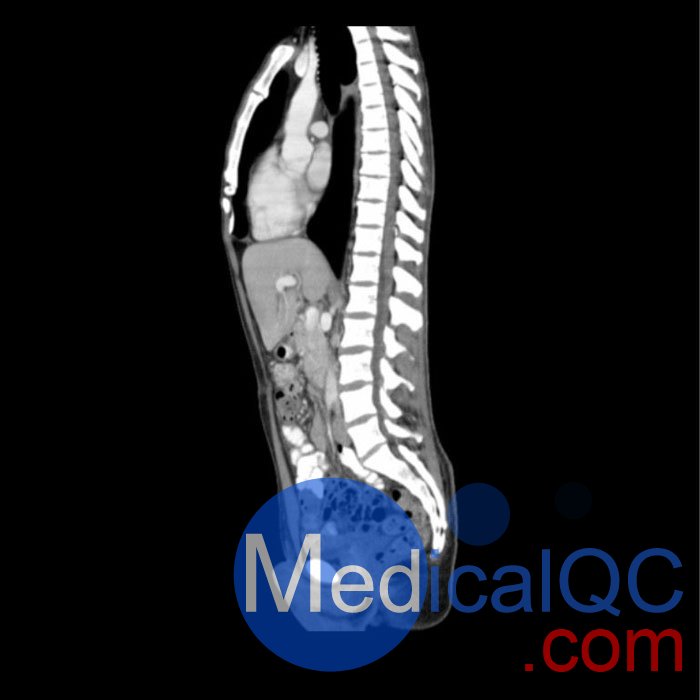

WEK57-01門靜脈期軀干模體,WEK57-01軀干模型模擬了門靜脈期的造影劑增強(qiáng)胸部、腹部和骨盆。它覆蓋了會陰的第二胸椎。

右側(cè)有髂淋巴結(jié)腫塊。

真實模擬脈管系統(tǒng)、骨骼和軟組織,包括肺、心臟、肝臟、膽囊、胰腺、脾臟、腎上腺、腎臟、胃、小腸、結(jié)腸、膀胱和前列腺。

右側(cè)髂外淋巴結(jié)腫塊。

WEK57-01門靜脈期軀干模體,WEK57-01軀干模型成像效果圖: